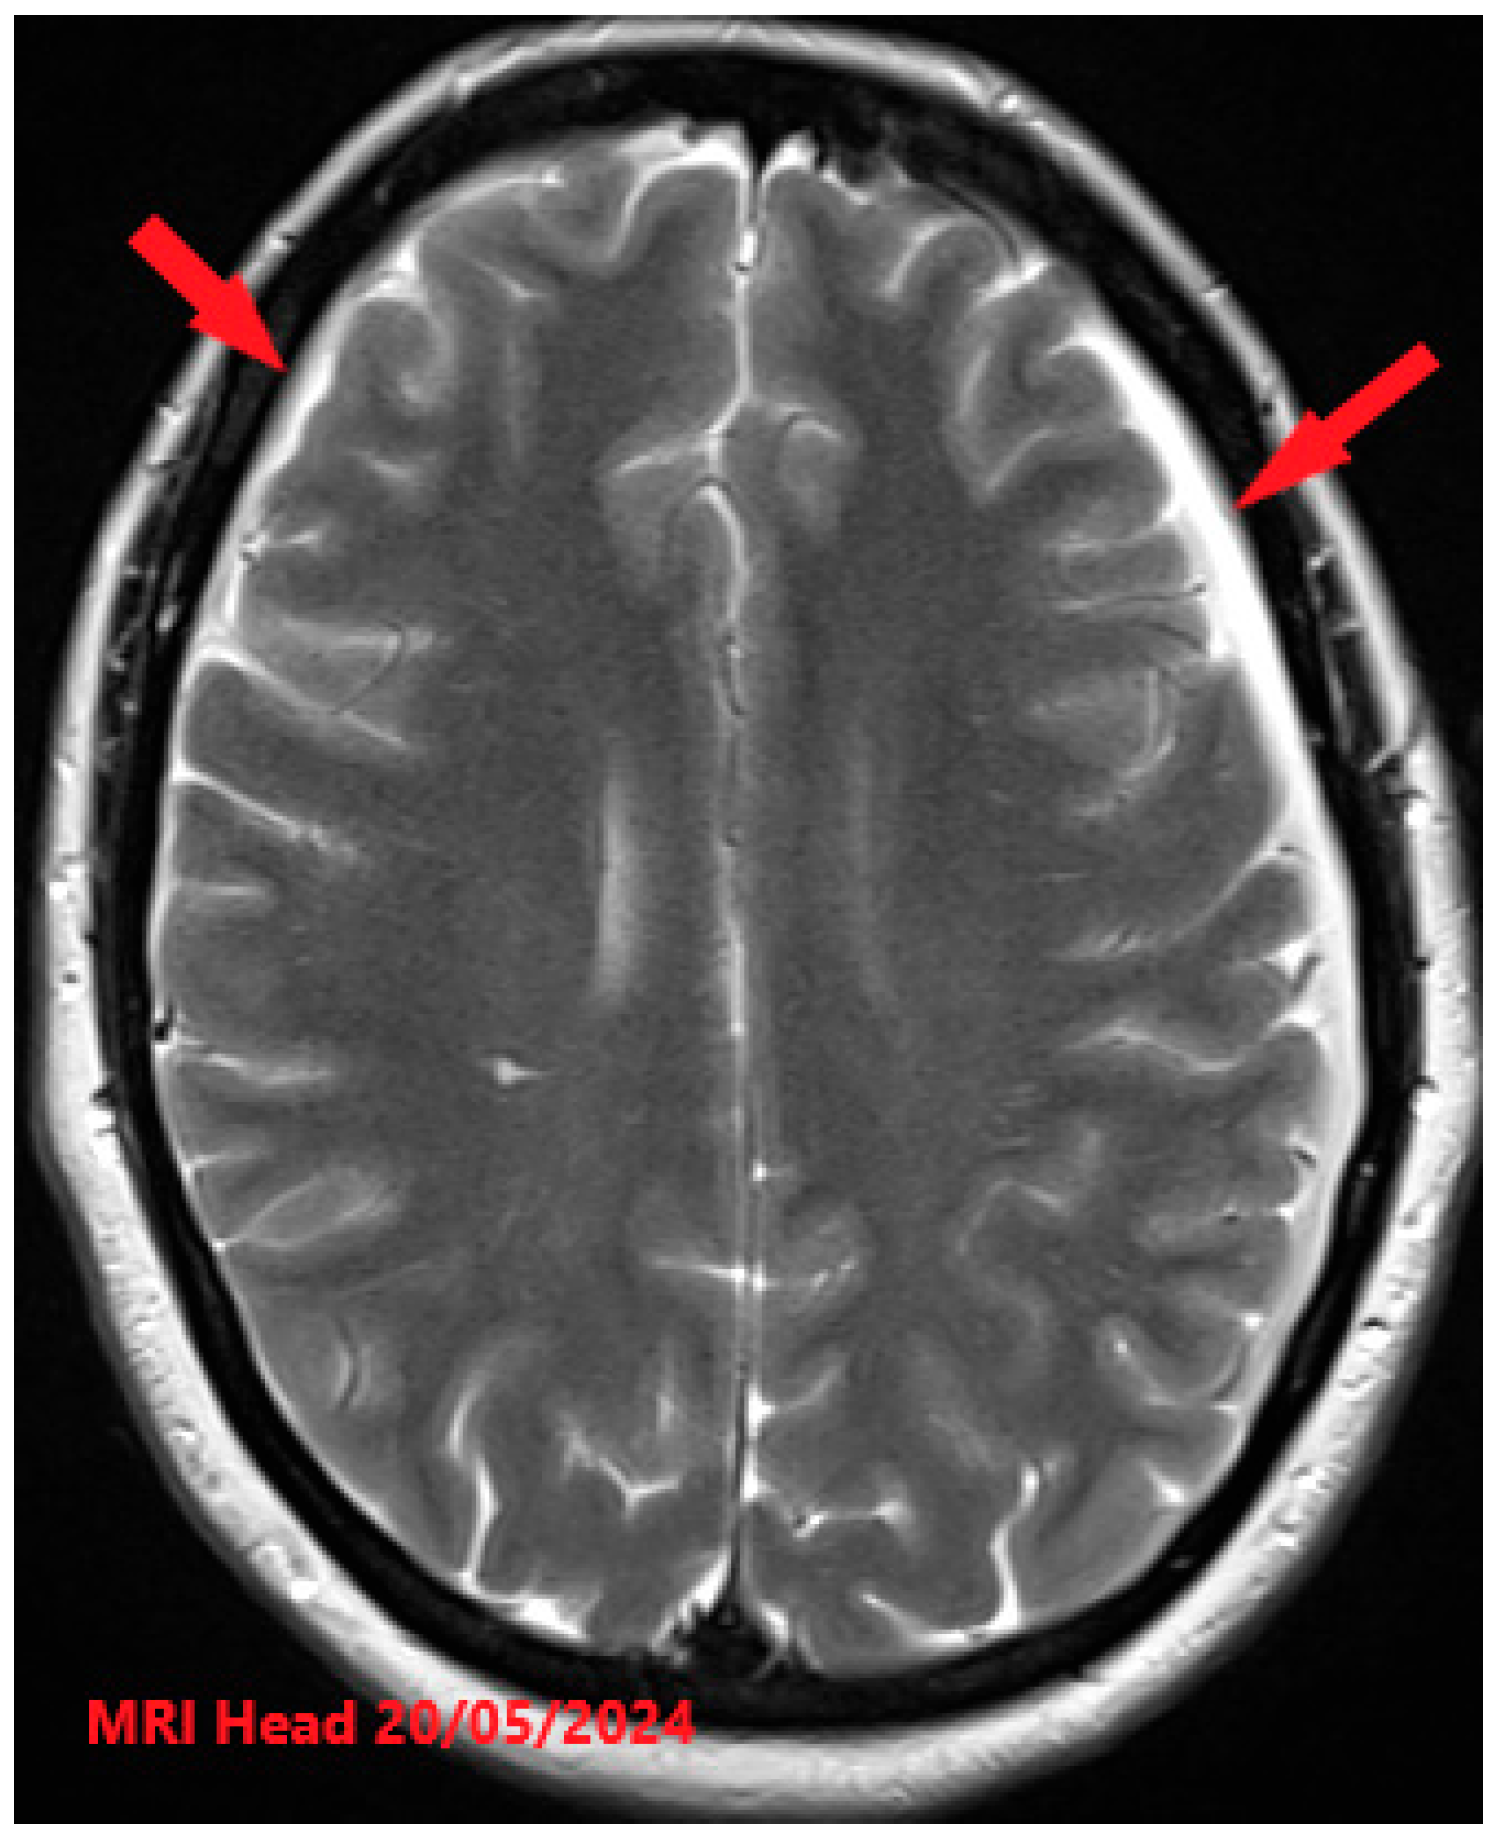

Figure 1. T2-weighted MRI Head with contrast axial view image findings showing initial presentation with significant bilateral subdural CSF collections (red arrows) and associated pachymeningeal enhancement and thickening.

She was then assessed by the local neurology team, including neurologists and neurosurgeons, who suspected low-pressure headaches and the possibility of a spontaneous leak. The local neurology multidisciplinary team recommended a repeat MRI head, spine, and orbits at 16 weeks and 3 days of gestation. MRI head, spine, and orbits demonstrated bilateral shallow subdural collections and extradural fluid within the spinal canal, meningeal thickening, and venous engorgement (Figure 1 and Figure 2). The case was discussed in a tertiary-level multidisciplinary team meeting for neuroradiology. A diagnosis of spontaneous intracranial hypotension was established based on the clinical presentation of a thunderclap headache with prominent postural features that worsened on standing, in conjunction with MRI findings of meningeal thickening. This was further supported by lumbar puncture results, which demonstrated xanthochromia and lymphocytic pleocytosis. She was then managed on the lines of treatment for spontaneous intracranial hypotension in pregnancy. She was initially managed with conservative management, including prolonged bed rest, adequate hydration, and avoidance of any strenuous activities such as bending, straining, with the aim of keeping the pain score below 4/10. She was started on prophylactic low molecular weight heparin to prevent the risk of venous thromboembolism in pregnancy. There was still no significant improvement in the headache with regular paracetamol and codeine. Her neurological examination as inpatient had always been unremarkable with no focal neurology.